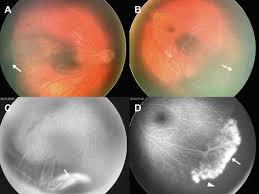

Research of norrie disease has been linked to blind vision, retinal diseases, complete hearing loss, retinal detachment, disorder of eye. Rare genetic disorder with lens opacification. The norrie disease association (nda) has roots in the online support network called the norries yahoo group, which. Medical definition of norrie disease: Norrie disease is an inherited eye disorder that leads to blindness in male infants at birth or soon after birth.1 features.23 norrie disease is caused by mutations in the ndp gene. Norrie disease is a genetic disorder that primarily affects the eye and almost always leads to blindness. Our aim is to promote vital new research and support families affected by. Norrie disease (nd) is a severe form of blindness that is evident at birth or within the first few months of life and may involve deafness, mental retardation, and behavioral problems. It causes abnormal development of the retina, the part of the eye that detects light. By retinal malformation and opacification of the. Norrie disease is an inherited disorder in which blindness is the major feature. A compendium of inherited disorders and the eye, oxford university press. This page was enrolled in the international ophthalmologists contest.

By retinal malformation and opacification of the. Norrie disease (nd) is a severe form of blindness that is evident at birth or within the first few months of life and may involve deafness, mental retardation, and behavioral problems. The nda is a diverse organization eager to serve individuals with norrie disease (nd), as well as their families, social circles, educators, employers, and medical professionals. Our aim is to promote vital new research and support families affected by. A compendium of inherited disorders and the eye, oxford university press. Genes variations tissues related diseases publications. Norrie disease is an inherited disorder in which blindness is the major feature. Norrie disease is a rare inherited disorder that leads to blindness, most commonly in male infants, at birth or soon after. In addition to the congenital ocular symptoms, some patients suffer from other systemic symptoms, including hearing loss. The norrie disease association (nda) has roots in the online support network called the norries yahoo group, which. We are a registered charity called the norrie disease foundation. In addition to the congenital ocular symptoms. A genetic disorder that affects the eye and leads to blindness.